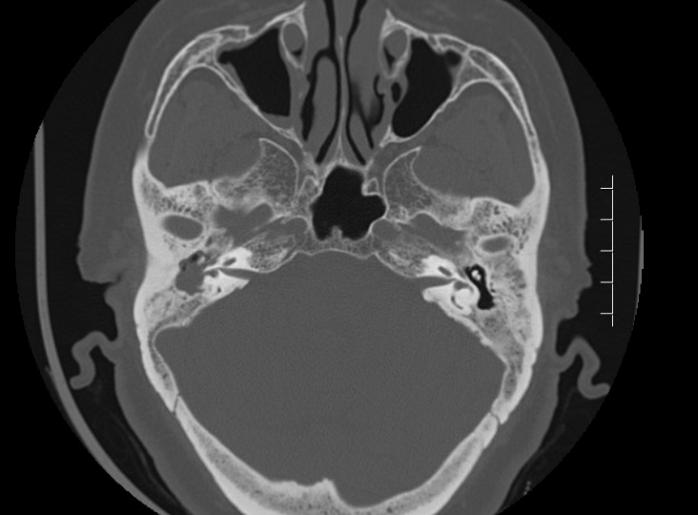

CT:顯示上鼓室骨質破壞,聽骨鏈被膽脂瘤壓迫吸收